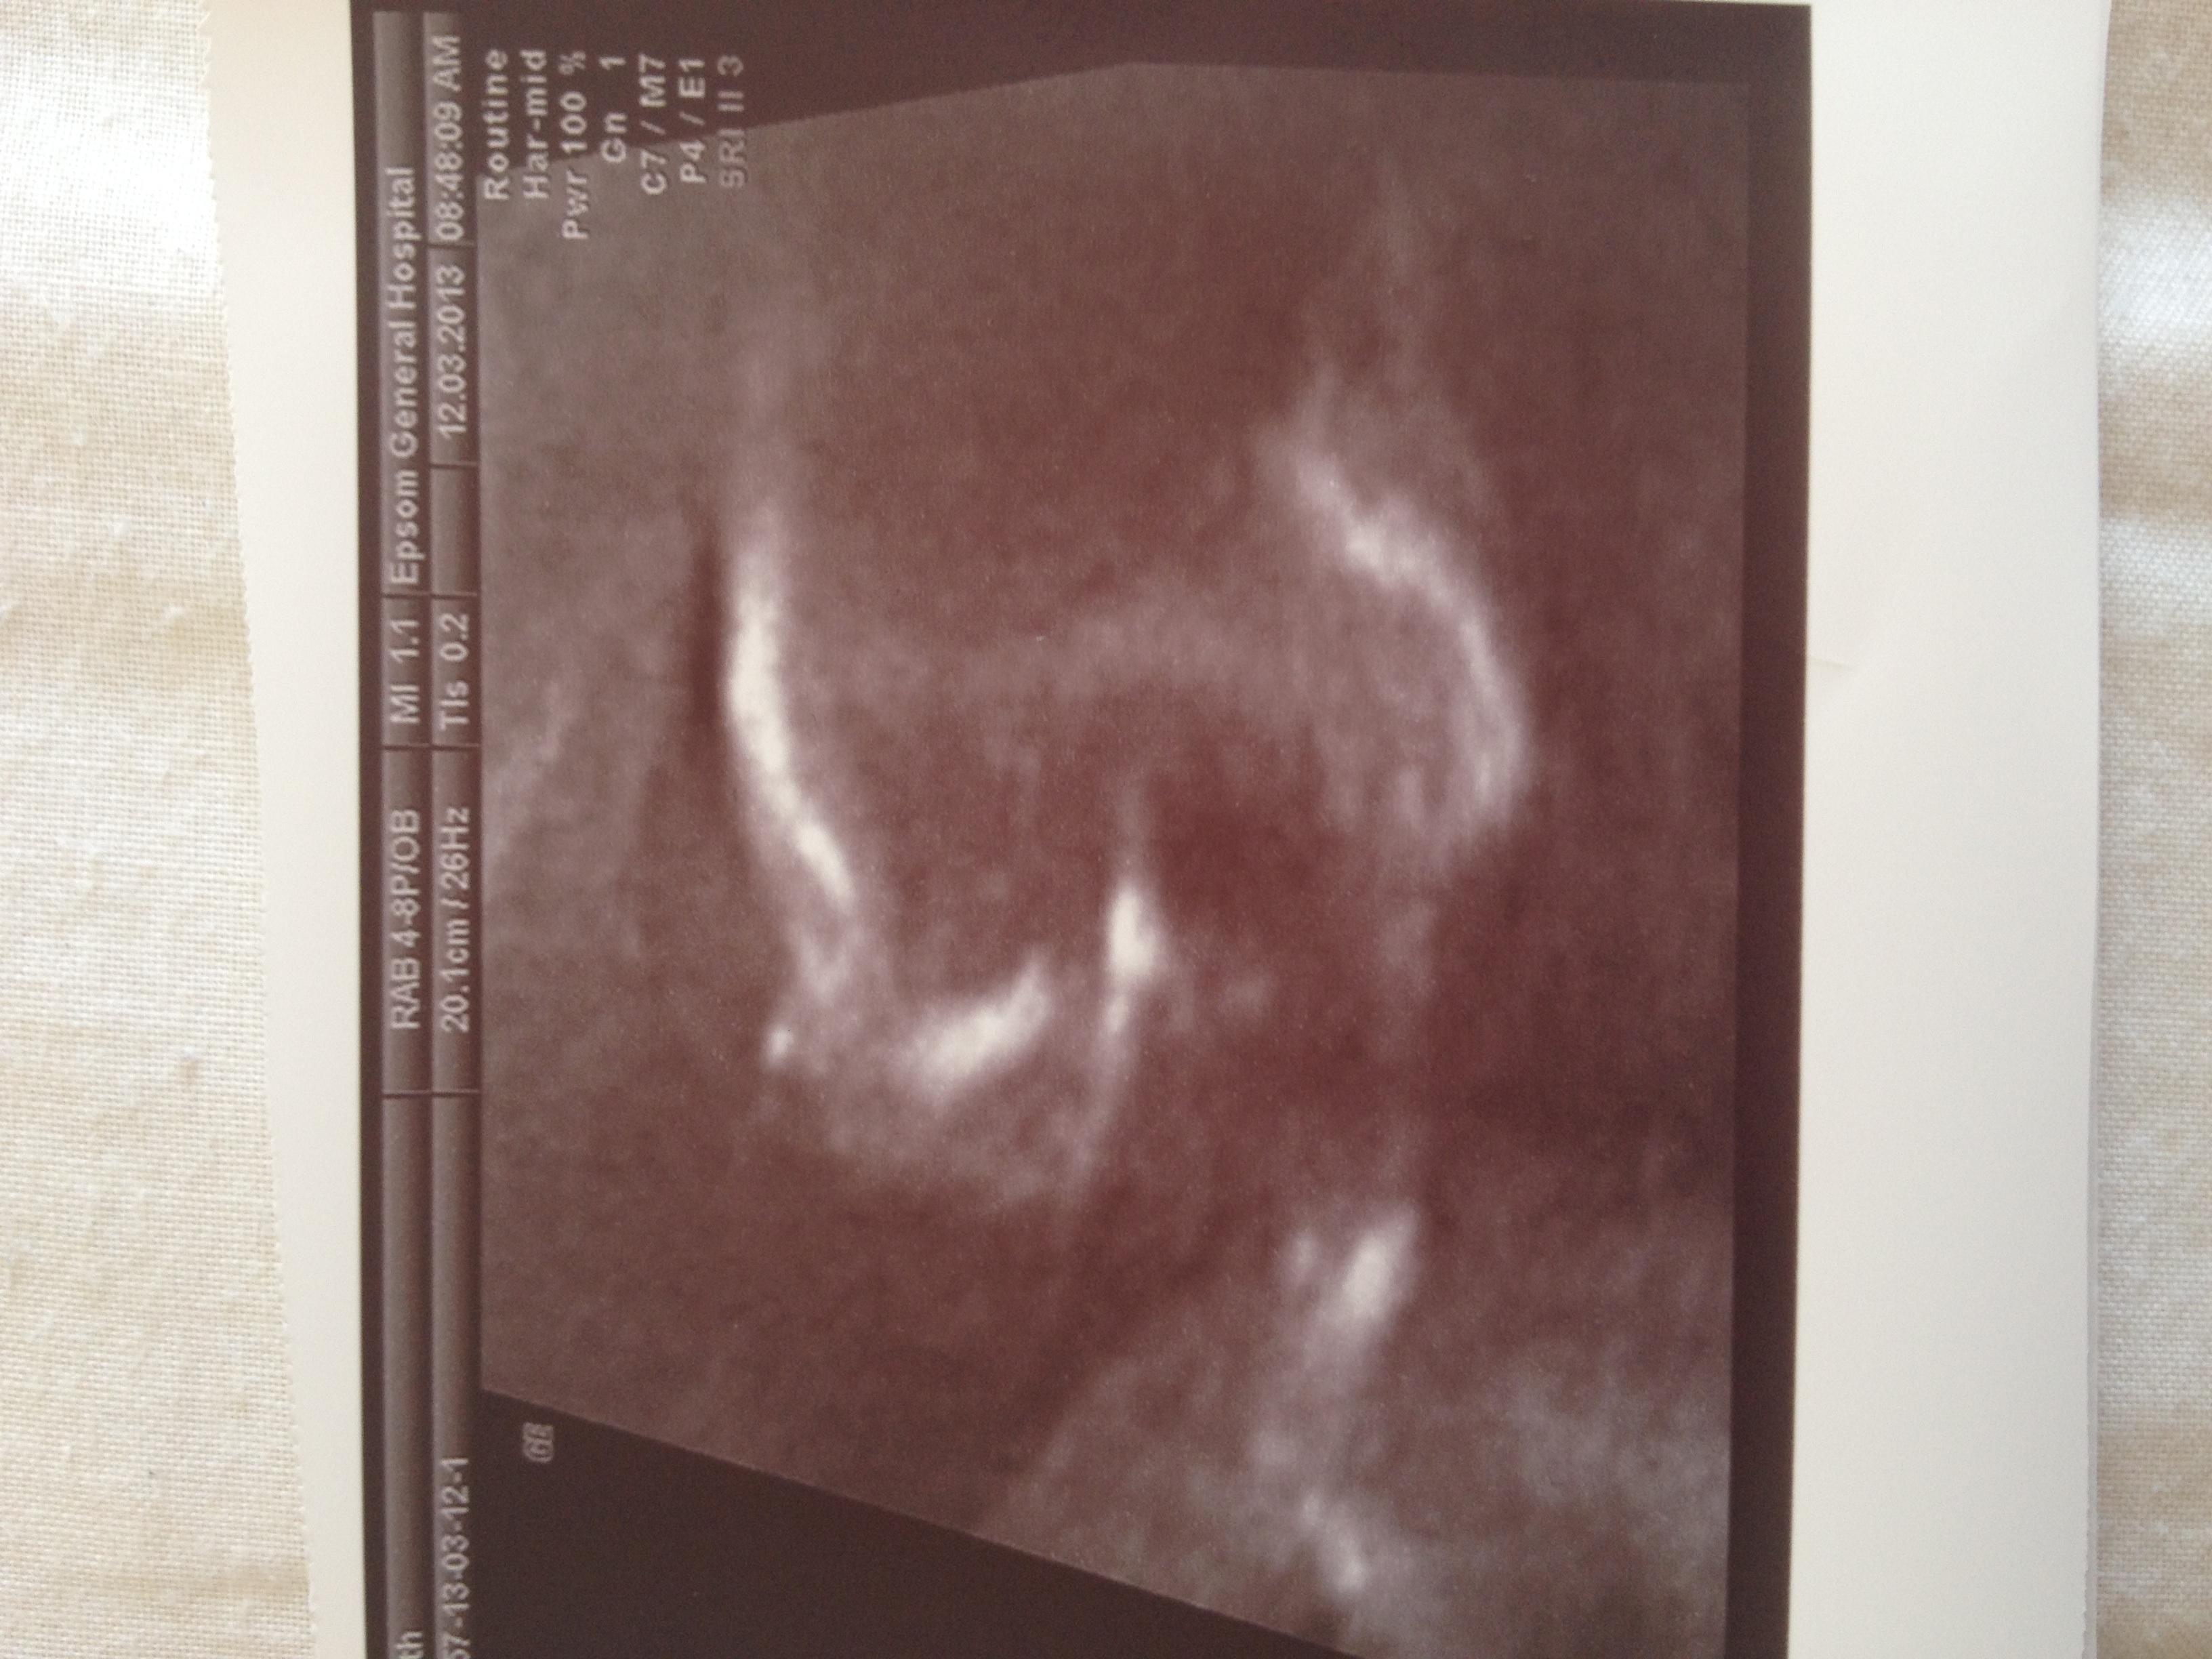

Attachment 10571

This is another pic I have- its sucking it thumb :)